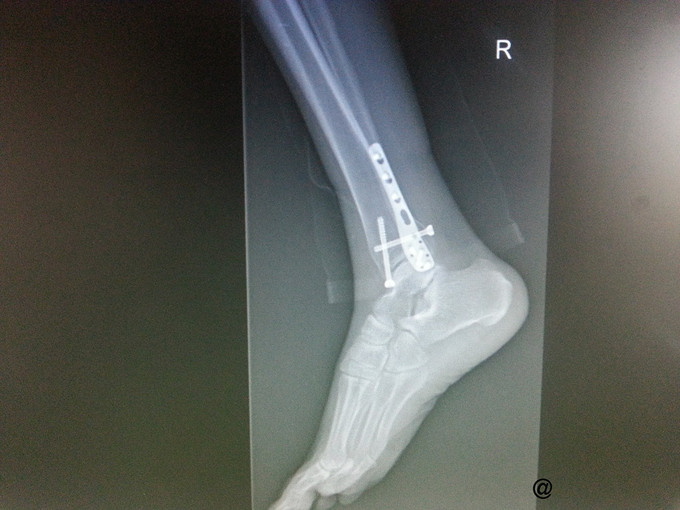

主诉:右三踝骨折ORIF术后一年半,要求取出内固定 病史:患者一年半前因外伤致右三踝骨折,1年前我院行“右三踝骨折ORIF术”。术顺,目前患者术后恢复良好,无切口处疼痛红肿热痛、无畸形愈合,为取出内固定再次入院。

查体:右侧外踝处可见一纵行8cm左右的陈旧性手术疤痕,愈合良好,踝关节无压痛,无肿胀,活动可。四肢肌力、肌张力正常。足趾自主活动良好,末梢血运正常,足背动脉搏动可及,皮肤感觉存在。其他肢体未见明显异常。 辅查:右侧踝关节正侧位片:右侧内外踝骨折内固定术后,内固定器在位,断端对位对线可。

诊断:取除骨折内固定装置(右三踝骨折术后) 处理:右踝关节骨折术后取内固定术